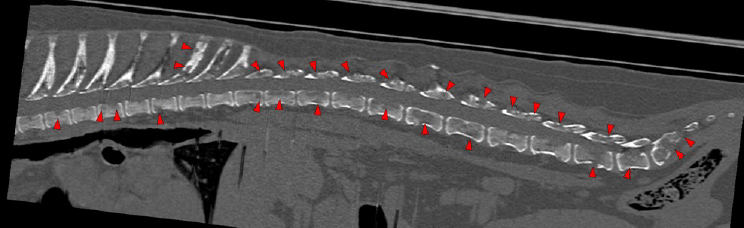

There are multiple osteolytic lesions affecting almost all the vertebral bodies (red arrows). Some of them are areas of permeative or moth-eaten lysis, while others converge into geographic lesions. They affect all the different portions of the vertebra (vertebral body, spinous and transverse processes, etc.) and involve the medullary cavity of the bone (blue arrows), and some of them cause lysis of the cortex (green arrows). Lumbar vertebral bodies more severely affected.

The osteolytic lesions have soft tissue attenuation that shows moderate and slightly heterogeneous post-contrast enhancement. In some of the vertebrae, the lesions cause lysis of the cortex and extend into the vertebral canal (orange arrows) causing variable degree of compression of the spinal cord and cauda equina (blue arrows). At the level of the vertebral bodies of T7, T8, T9 and T12 the lesions extend into the ventral and central aspect of the vertebral canal causing a mild compression of the spinal cord. At the level of T13, L1, L4 and L5 the lesions extend into the ventral and central aspect of the vertebral canal, causing moderate compression of the spinal cord. At the vertebral body of L6 the lesion extends into the ventral and central aspect of the vertebral canal, at the mid-aspect of L6, occupying approx. 90% of the diameter of the vertebral canal causing a severe compression of the cauda equina. At the level of L7, the lesion extends into the ventral and both lateral aspects of the vertebral canal, causing severe compression of the cauda equina.

There are multiple osteolytic lesions with the same characteristics affecting both scapula and the pelvic bones included (pink and blue arrows respectively). There are osteolytic lesions with the same characteristics affecting multiple ribs. Associated with these lesions, there are multiple rib fractures.